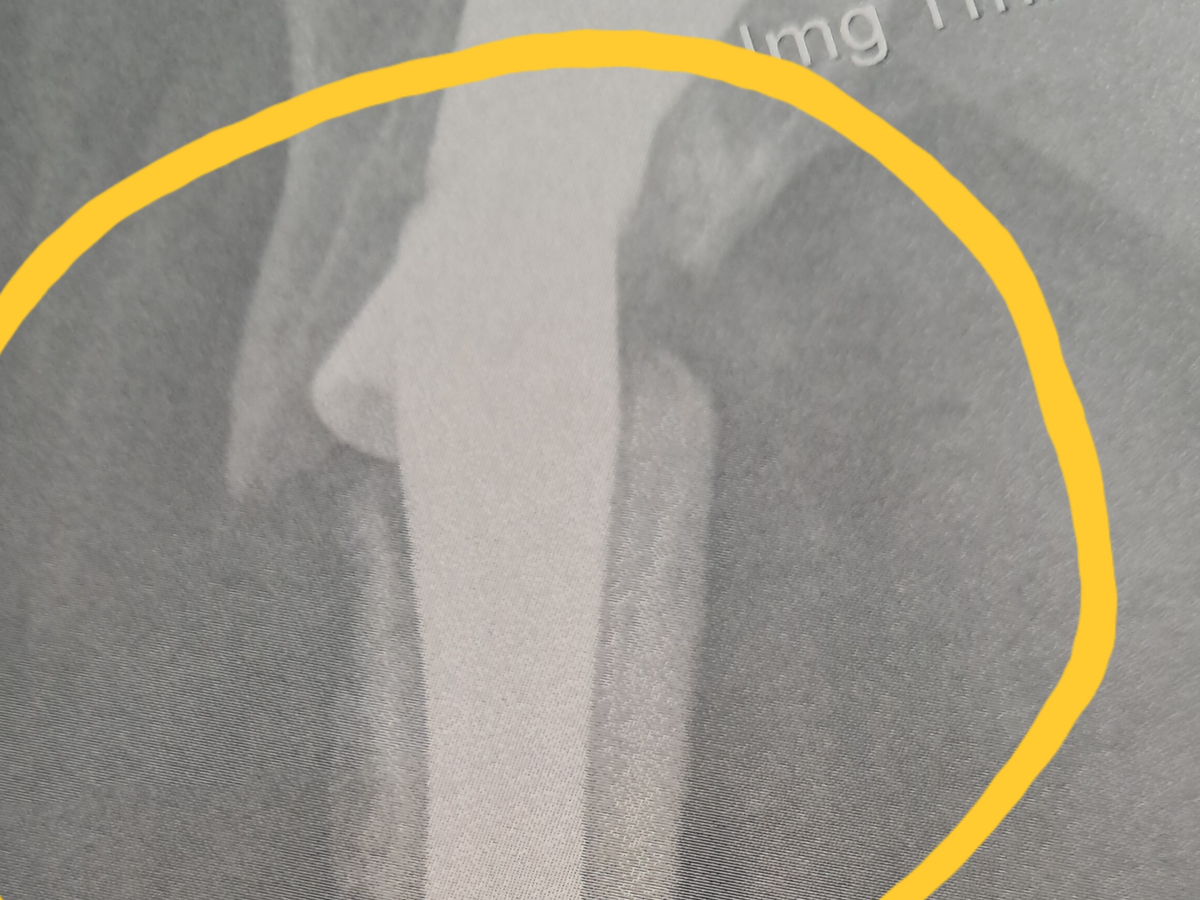

I am currently in the Dominican Republic and have suffered a catastrophic injury involving a broken hip and femur, resulting in my leg being effectively detached from the hip due to non-union. This is my third major femur-related injury in the past 14 months.

In November 2024, I suffered a serious fall in my home that resulted in a femur fracture requiring surgical intervention and the insertion of an intramedullary rod. After months of recovery, the rod re-fractured six months later while I was in the Dominican Republic, requiring a second surgery to remove and replace the hardware.

Unfortunately, due to undiagnosed osteoporosis, my bones failed to heal properly. I have now suffered a third and most severe injury: a broken hip and femur with hardware failure and non-union. I have been advised that I require an urgent total hip replacement and complex reconstructive surgery in order to walk again and to prevent further life-threatening complications.